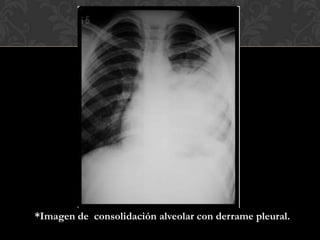

 En las radiografías los infiltrados son con frecuencia densos y

bien circunscritos.

 El aspecto radiográfico puede confundirse con Ca pulmonar.

 Puede afectar múltiples lóbulos.

 Puede encontrarse un patrón fibronodular e infiltrados

alveolares.

*Imagen de consolidación alveolar con derrame pleural.